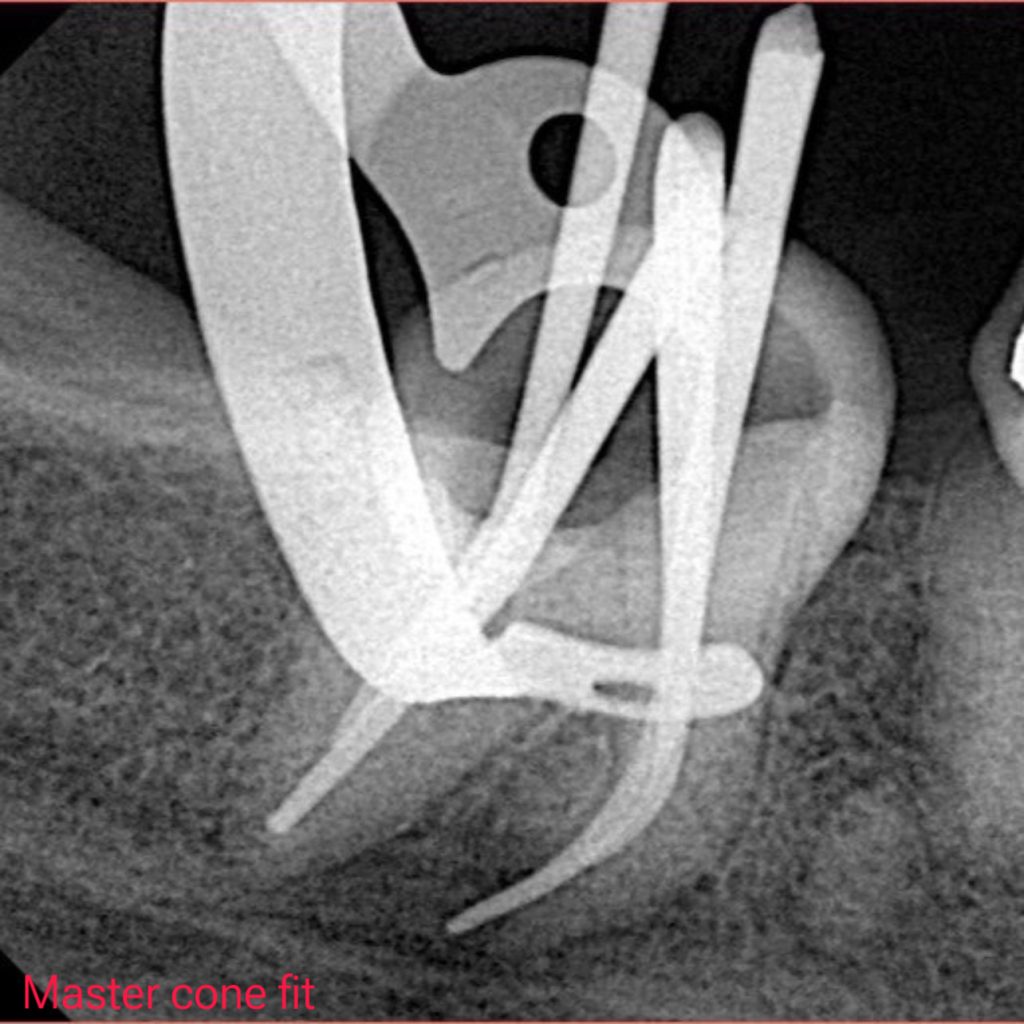

X ray showed many problems in previous Endodontic treatment with overhang amalgam filling

– Endodontic Re-treatment done, Obturation with Bioceramic Sealer and single cone